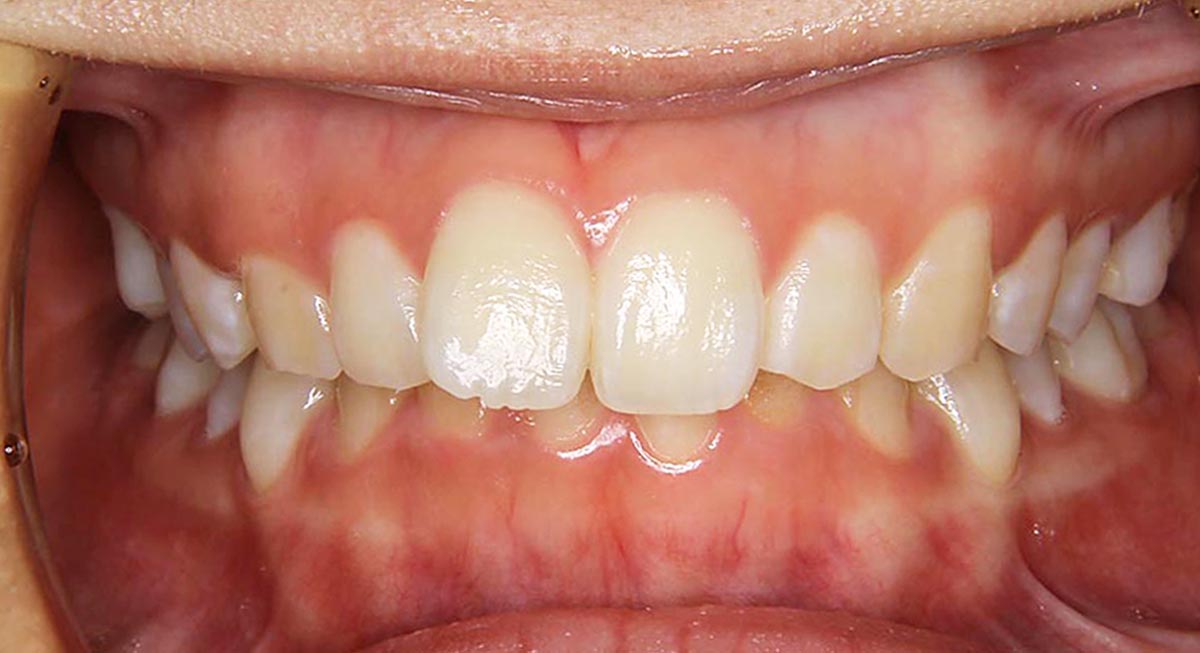

上下顎前突症例

●主訴

歯のデコボコが気になる

●診断

AngleⅠ級・上下顎前突

●治療に用いた主な装置

上顎にリンガルブラケット矯正装置、下顎にマルチブラケット装置(ハーフリンガル)

●抜歯部位

上下左右第一小臼歯

●治療期間

2年6ヶ月

●治療費用

約113万円(ともに税込、調整費、保定費まで含む総額制)